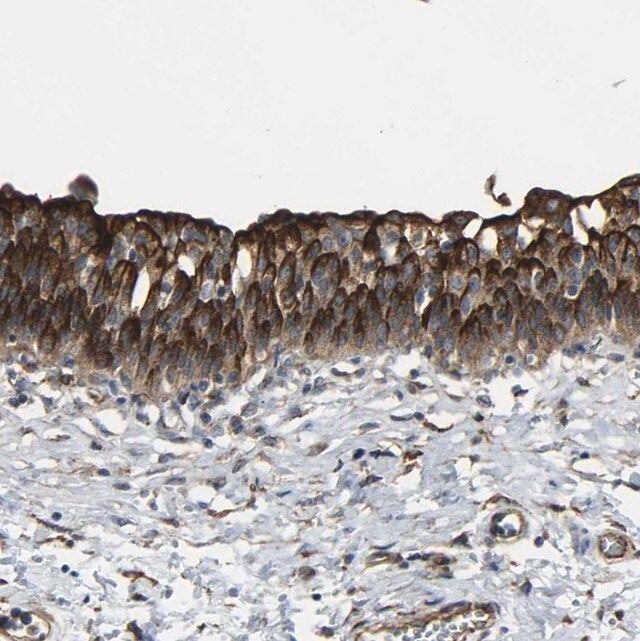

The gene MYOF (myoferlin) encodes a type II membrane protein that shares homology with dysferlin. It is predominantly expressed in developing muscle and extensively in cardiac muscle. It is a member of the ferlin family of proteins. These proteins contain C2 domains that are important in calcium-mediated membrane fusion events. Myoferlin is found to be associated with both plasma membrane and nuclear membrane.

Anti-MYOF antibody produced in rabbit, a Prestige Antibody, is developed and validated by the Human Protein Atlas (HPA) project (www.proteinatlas.org). Each antibody is tested by immunohistochemistry against hundreds of normal and disease tissues. These images can be viewed on the Human Protein Atlas (HPA) site by clicking on the Image Gallery link. The antibodies are also tested using immunofluorescence and western blotting. To view these protocols and other useful information about Prestige Antibodies and the HPA, visit sigma.com/prestige.

Myoferlin is involved in the fusion of endomembrane with the plasma membrane in muscle cells and endothelial cells. It forms a complex with dynamin-2 (Dyn-2) and promotes the surface expression of vascular endothelial growth factor receptor 2. The protein complex of myoferlin-Dyn-2-Cav-1 (caveolin-1) participates in the processes of membrane fusion and fission. Myoferlin is also implicated in receptor-dependent endocytosis. It is crucial for muscle development and regeneration, and its expression is found to increase in skeletal muscle on injury. It participates in vesicle recycling and its deficiency can lead to accumulation of transferrin in the perinuclear endocytic recycling compartment in the myoblasts. It regulates postnatal muscle growth mediated by IGF1 (insulin-like growth factor 1).